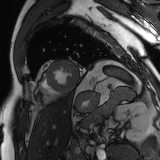

Refer to caption

Figure 2: Examples of tracking results using the proposed method (MPN-C). From left column to right: ED frame, ES frame, warped frame from ED, overlay of ES frame and the warped mask, and estimated motion field using HSV color coding. The color coding wheel legend indicates the motion directions.